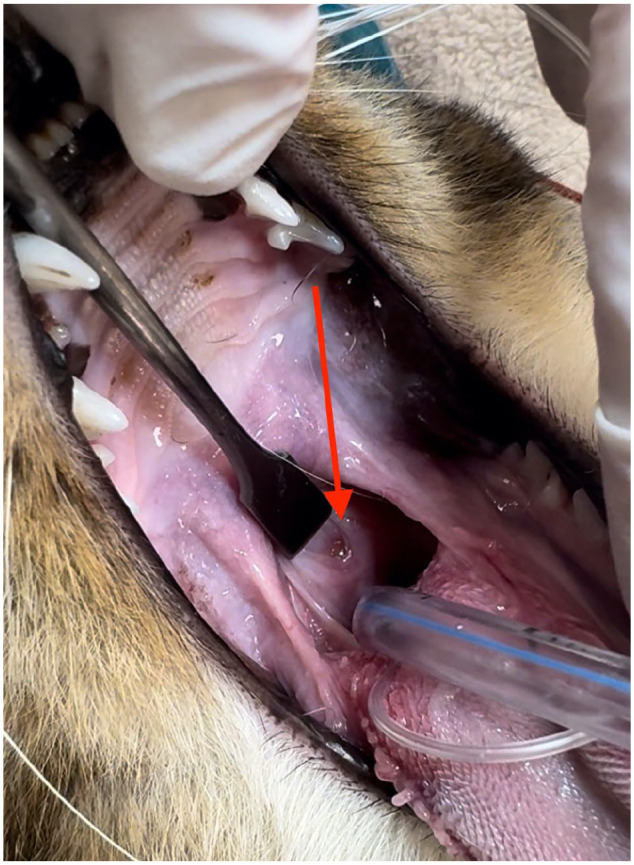

Case summary: A female intact domestic shorthair kitten was evaluated at 8 months of age for bilateral mucopurulent nasal discharge, stertor, open-mouth breathing and difficulty eating. Imperforate nasopharynx (INP) was diagnosed on oronasal examination under anesthesia. An extended palatoplasty was performed and resulted in resolution of the clinical signs.

Relevance and novel information: The extended palatoplasty procedure is relatively simple and very similar to the correction of soft palate elongation in brachycephalic dogs. It does not require special equipment and materials; therefore, it represents a viable, more readily available and cost-effective option for the treatment of INP. To the author's knowledge, this is the first case of INP that has been treated with extended palatoplasty.